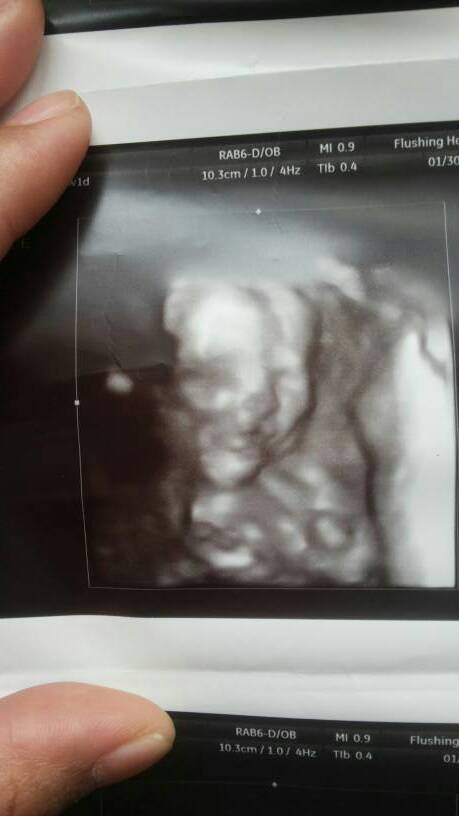

20周做了三维排畸检查,医生说挺好,但是回家我看宝宝有两张照片总觉得有点像唇裂,另外两张好像又没有

20周做了三维排畸检查,医生说挺好,但是回家我看宝宝有两张照片总觉得有点像唇裂,另外两张好像又没有,担心。

你好,你应该是太担心了。医生检查说没有异常应该就没有问题。医生在看的时候是动态的,可以多个角度来看,一般来说做出的诊断比较可靠。我们看到的报告单上的图片是个静止的,看影像可能会受到角度的影响,不能做出明确诊断。如果实在不放心,可以在以后的孕检中让医生再多注意一下胎儿的颜面部。

建议你下次去产检把照片带给医生看看,问个清楚,省的你胡思乱想啊

感觉三维或四维的照片拍的都很丑,宝妈不要担心,有的时候照片拍不好,医生也不敢马虎乱说